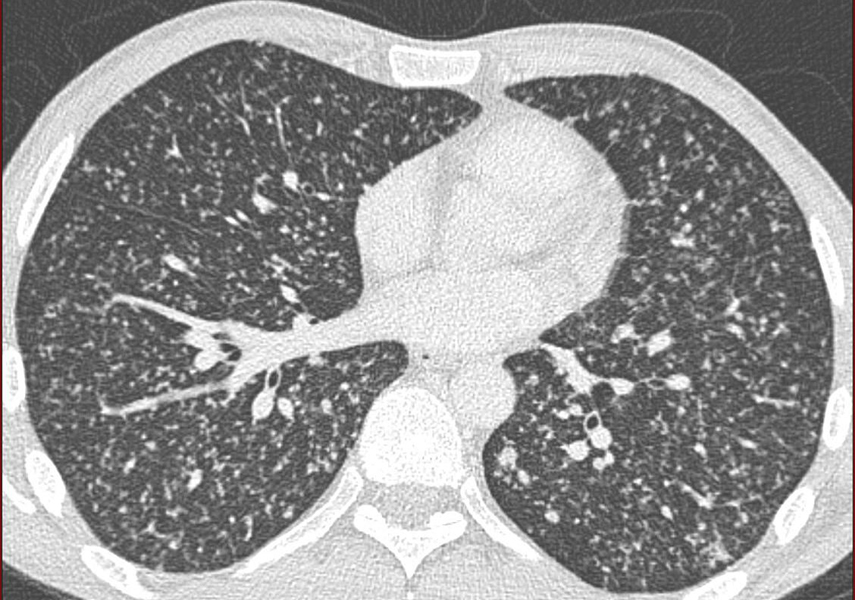

Eleveur d’oiseau. lésion élémentaire? Diagnostic?

Nodules de contours flous. pneumopathie d’hypersensibilité